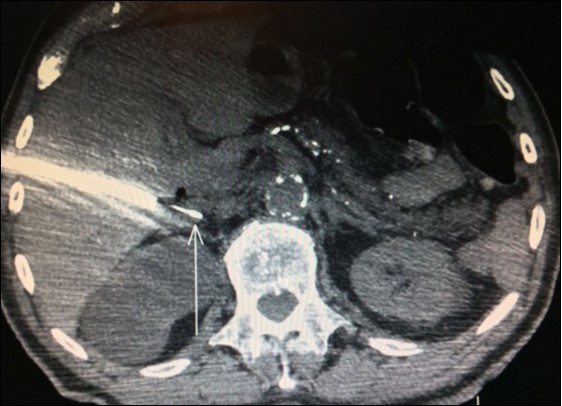

Usually, the imaging screening used for diagnosis of adrenal metastasis are: CT scans (Figure 1), magnetic resonance imaging (MRI) and PET-CT. The sensitivity of PET-CT has conflicting results, being of 96% and with false-positive detection rate even for smaller masses (without swelling and not evident on CT or MRI) of only 4% as reported in some series8,9,18. Another study confirms these findings, showing sensitivity and specificity of PET/CT for distant metastasis of 94% and 85%, respectively31.

Figure 1.CT scan showing isolated right adrenal NSLC metastasis (Arrow)

Adrenal biopsies (Figure 3) before adrenalectomy is useful in order to identify the nature of the lesion10,11,12. Even with fine-needle aspirate is possible a diagnosis and also a successful molecular testing by next-generation sequencing in order to the identification of pathogenic alterations linked to available or developing targeted therapies30.

Figure 3.Right adrenal needle biopsy (arrow)